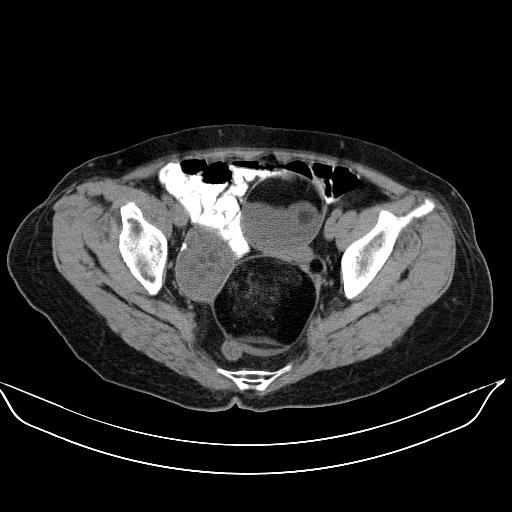

标题: CT17892:盆腔肿块

患者,女,61岁,无自觉症状,体检时发现盆腔肿块。

盆腔内多发性畸胎瘤。

典型畸胎瘤(皮样囊肿)